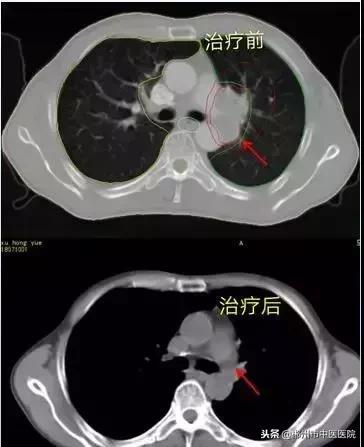

患者谢某,男,48岁,因“头晕、头痛2月,发现颅内肺部占位1月”,病检报告示:小细胞肺鳞癌。头颅核磁共振示:右侧桥小脑角区、小脑蚓部、右额叶、左颞叶、左侧基底节区及左侧岛叶后部多发占位病变,多考虑转移瘤。患者于2018年7月16日在我科行陀螺刀治疗,患者治疗后三个月的对比图如下: